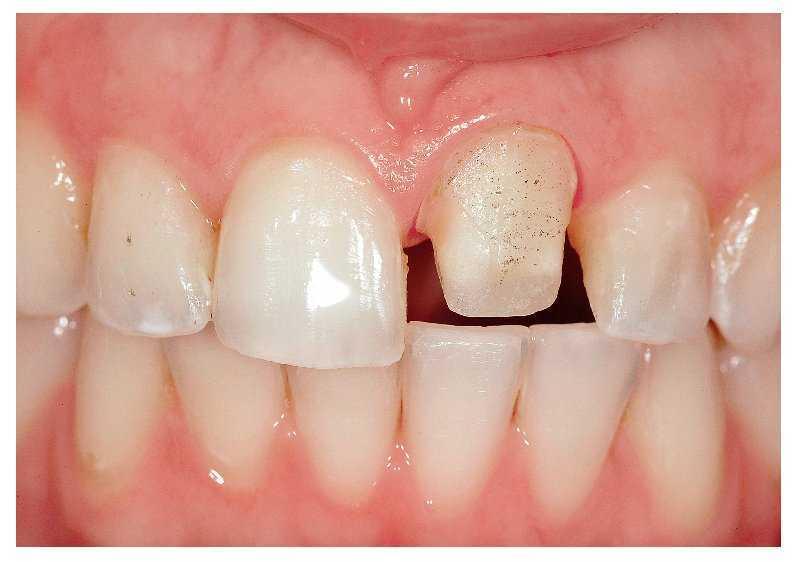

Un hombre de 46 años con un puente en el maxilar inferior izquierdo y una caries recurrente bajo el premolar deseaba una solución protésica con dientes separados. La anamnesis arrojó resultados normales. Un puente de 20 años de antigüedad reponía el diente 36 ausente.

El paciente se quejaba de dolores al masticar y de una sensación de aflojamiento alrededor del pilar de puente mesial (fig. 6a).

Fig. 6a. El puente en el maxilar inferior izquierdo, resulta visible una caries recurrente en el premolar 35.

En la radiografía se puso de manifiesto la necesidad de un tratamiento endodóntico del premolar. Tras el alivio de los dolores objeto de la queja original y una vez realizado el tratamiento endodóntico se reconstruyó el diente de forma conservadora (fig. 6b). Desde hace ya un siglo, las supraestructuras de espiga radicular coladas constituyen la rehabilitación estándar para dientes sometidos a endodoncia12,21,38,54,74. También pueden utilizarse espigas radiculares prefabricadas, puesto que su resistencia a la flexión es muy similar a la de la dentina, de modo que refuerzan la raíz y reducen el riesgo de fractura radicular10,17,35,58,66,69,72.

Fig. 6b. El premolar ha sido sometido a endodoncia y provisto de una espiga radicular Peerless-Post (SybronEndo, Orange, California, EE. UU.).

Ante una extracción dental, antaño se otorgaba poca importancia a la conservación de la cresta alveolar y de la pared ósea bucal. No obstante, si se desea que el implante conserve la sustancia ósea y garantice la función correcta de la rehabilitación protésica, se requiere el máximo esmero para (1) la preparación del punto de extracción, (2) la ejecución correcta de la extracción en la técnica escogida y (3) la restauración del tejido blando. Incluso en caso de inserción de un único implante utilizando componentes prefabricados o prefabricados-confeccionados (figs. 6c y 6d), son muy importantes la dirección de inserción del pilar y de la corona definitiva. Al dar los contornos correctos a estos componentes no sólo se mejora el efecto estético, sino que se contribuye también a lograr unas condiciones periodontales y periimplantares ideales (figs. 6e y 6f).